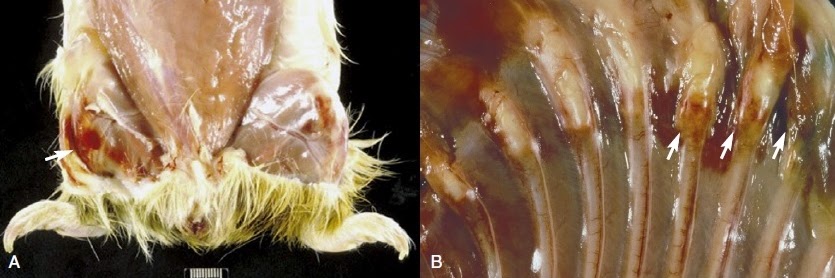

Cistos e tumores ovarianos